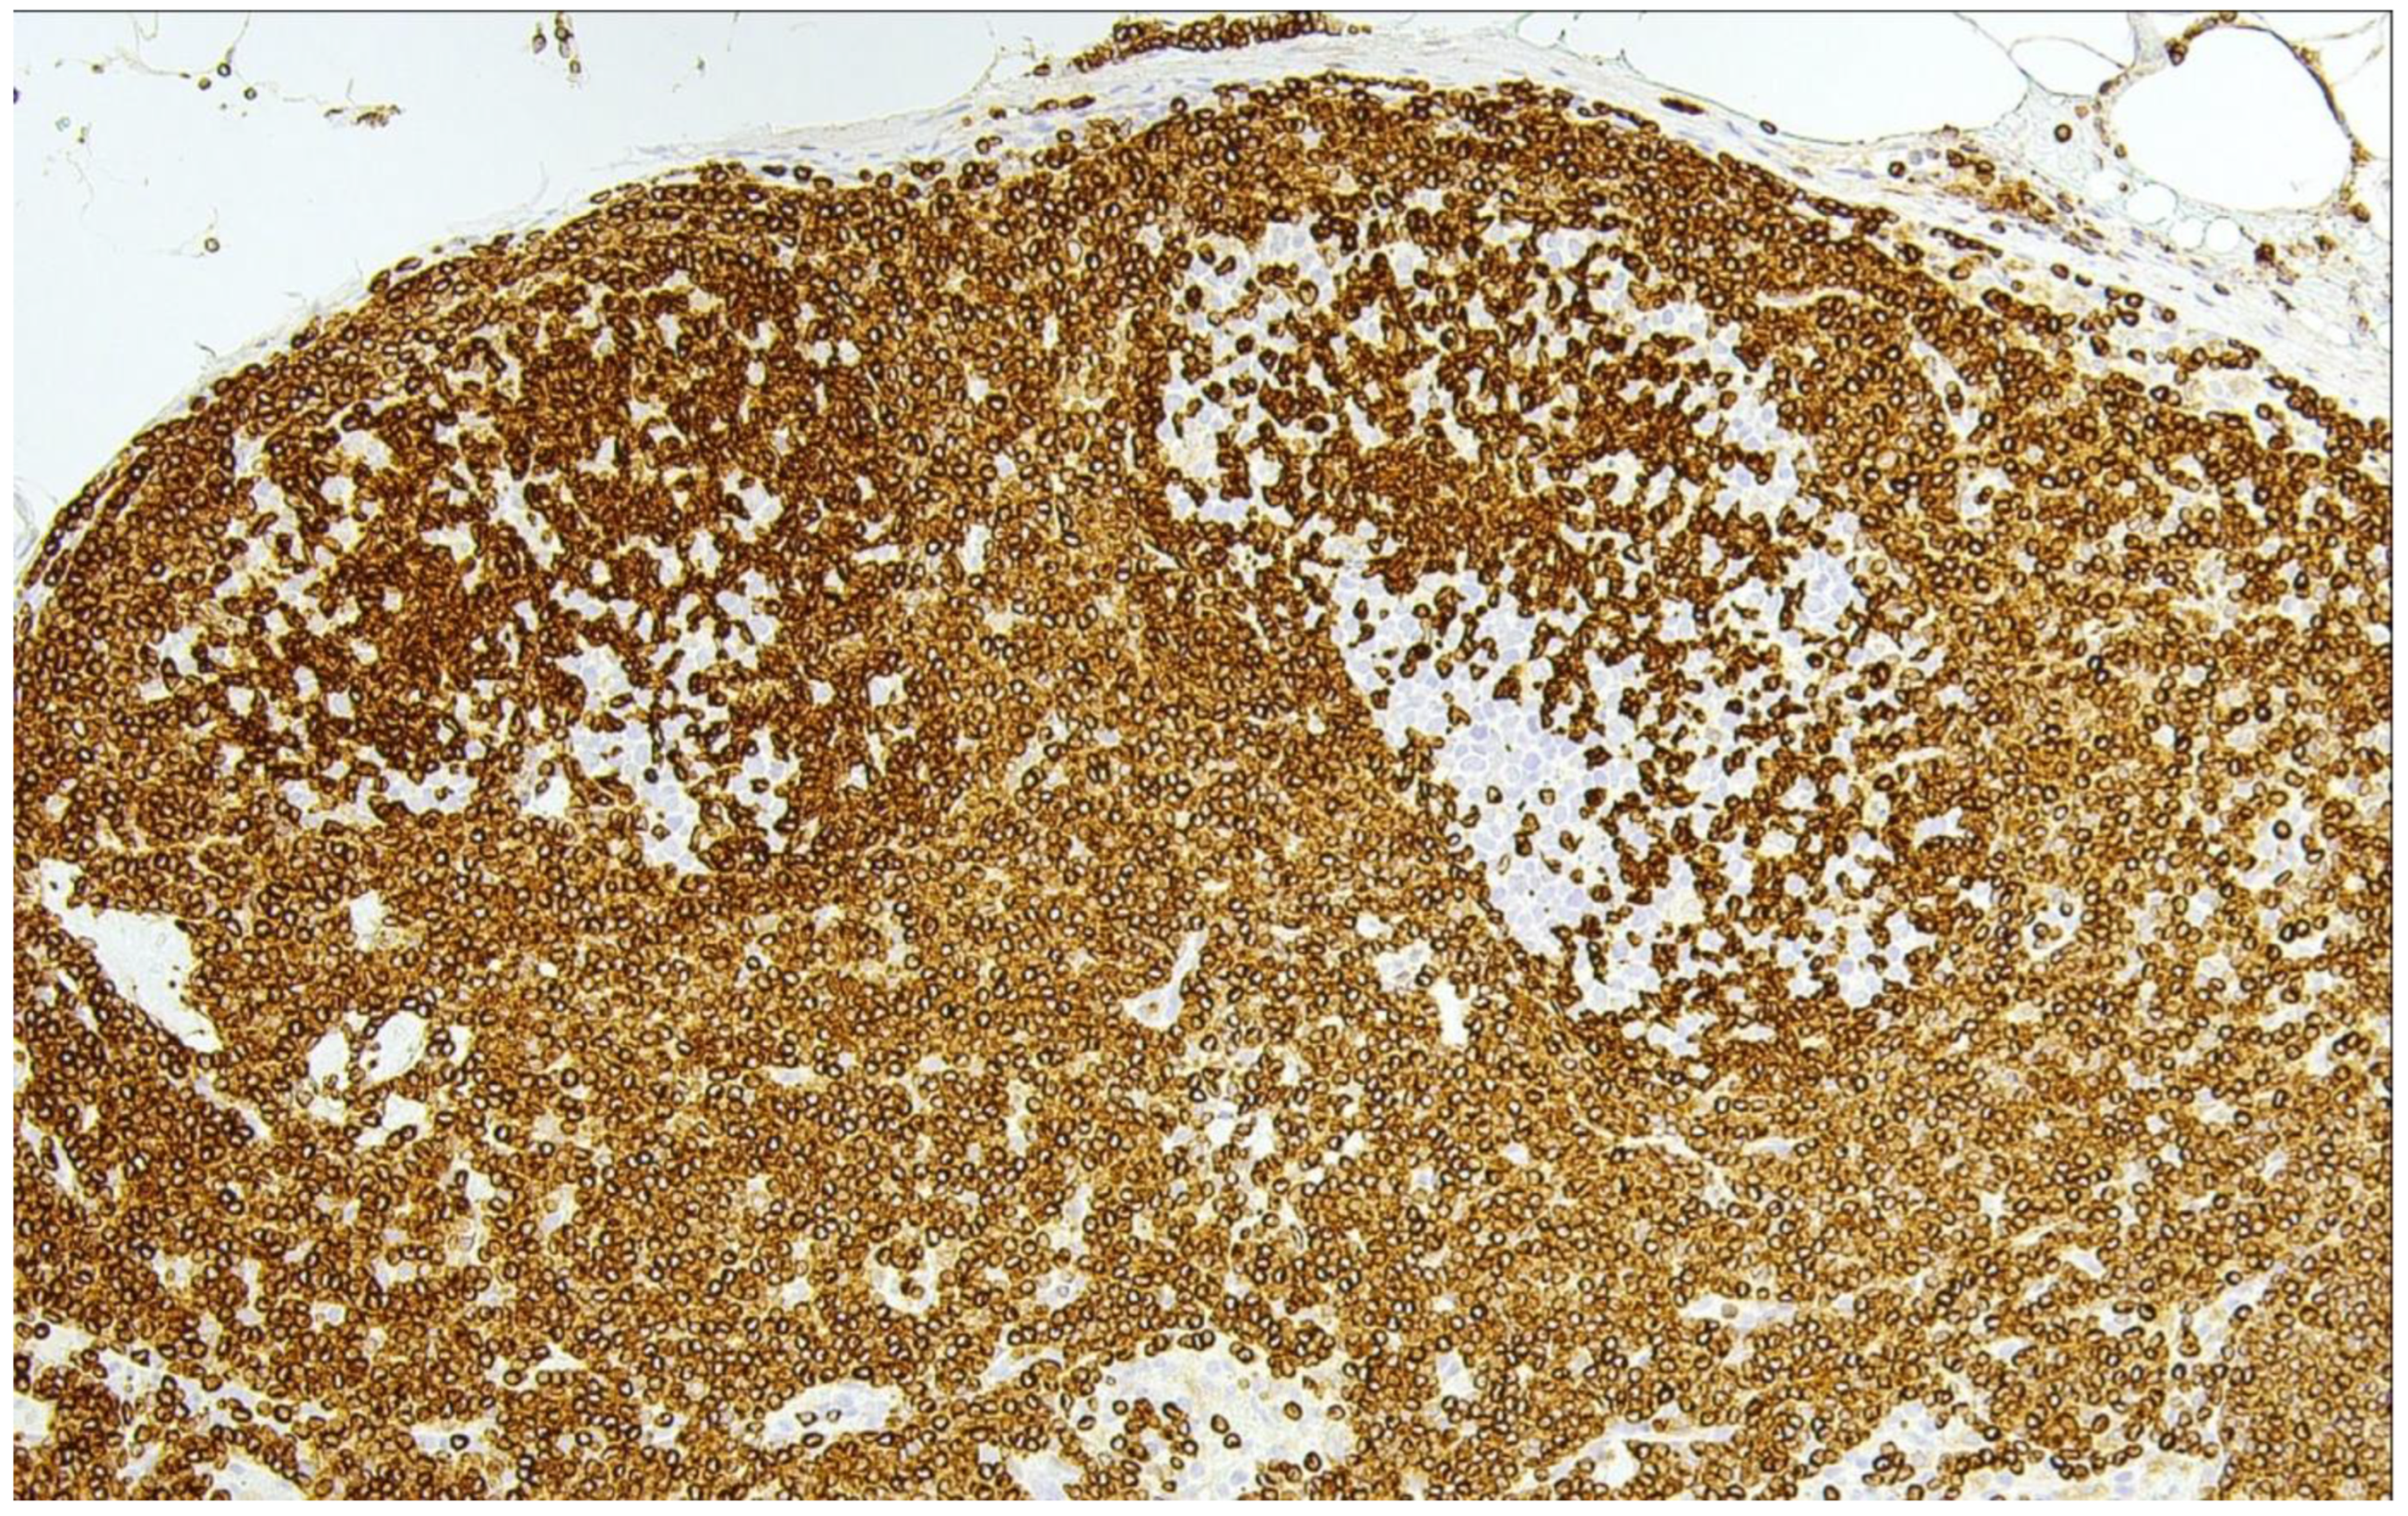

6. Predominantly Diffuse FL